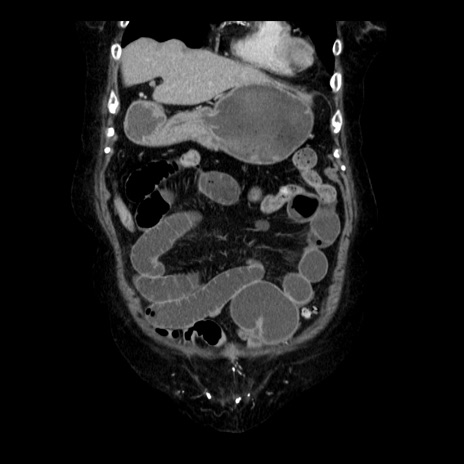

症例14(冠状断像)

【症例】 90歳代女性

【主訴】 腹痛・嘔吐

【現病歴】今朝から左側腹部痛を認めた。 経過観察していたが、嘔吐を認めたため来院。

【既往歴】 子宮癌術後

【身体所見】 意識清明、BP 127/54mmHg、P 98bpm Sp02 95%(RA)、BT 35.8°C、腹部平坦・軟腸ぜん動音聴取良好、右下腹部圧痛(+) 反跳痛なし

【データ】WBC 9800、CRP 0.46